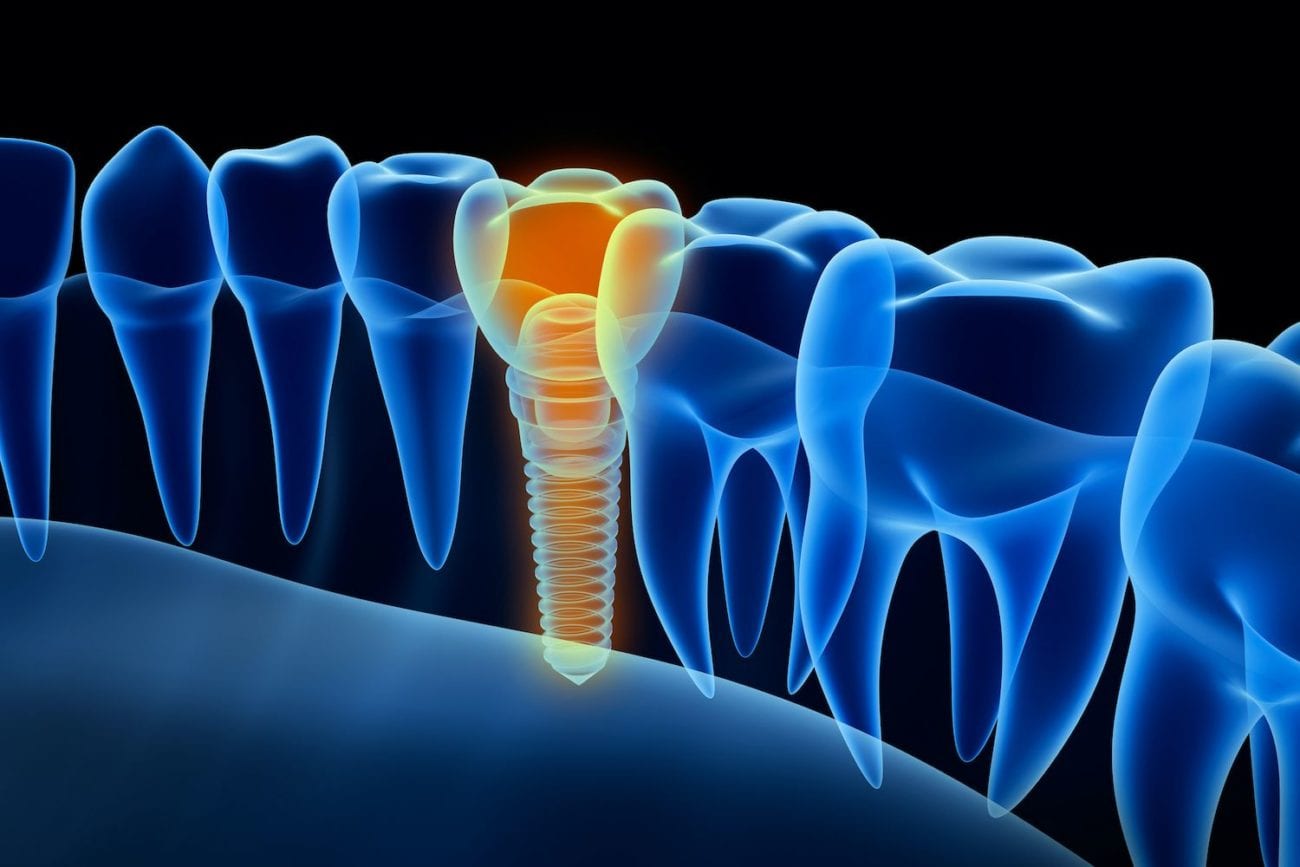

Зубы на черном фоне: Визуализация стоматологических изображений

Раздел: Необычные решения